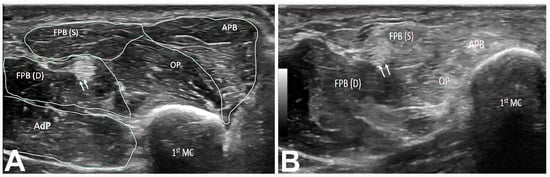

The APB and OP muscles were hyperechoic in 225 (99.6%) hands, while the FPB muscle was hyperechoic in 29 (12.8%) hands (Table 7). Of the 29 hands with a hyperechoic FPB muscle, 24 (82.8%) hands had total thenar muscle atrophy and 5 (17.2%) had partial thenar muscle atrophy. A total of 104 (46.0%) hands had a wrist CSA between 10 and 20 mm2, and 119 (52.7) hands had a wrist CSA greater than 20 mm2. The forearm CSA was between 3 and 6 mm2 in 102 (45.1%) hands, between 7 and 10 mm2 in 104 (46.0%) hands, and greater than 10 mm2 in 20 (8.9%) hands. The Heckmatt grade determined by US was 3 in the majority (152 [67.3%)] of hands, with 204 (90.3%) hands having a grade of 3 or 4 (Figure 6; Table 8). Of the 152 hands with a grade of 3, 129 (84.9%) had partial thenar atrophy and 23 (15.1%) had total thenar atrophy (Table 8). Of the 52 hands with a grade of 4, cases were evenly divided between total and partial thenar atrophy.

Figure 6. (A) Short axis of right thenar muscles (Heckmatt grade 1). The double arrow indicates the FPL tendon. (B) Short axis view of right thenar muscles (Heckmatt grade 3) showing hyperechoic APB, OP, and FPB(S) muscles. Note the normal appearance of the FPB(D) muscle. The double arrow demarcates the FPL tendon. 1st MC: first metacarpal bone. APB: abductor pollicis brevis muscle. OP: opponens pollicis muscle. FPB: flexor pollicis brevis (S: superficial head; D: deep head). AdP: adductor pollicis muscle. FPL: flexor pollicis longus.